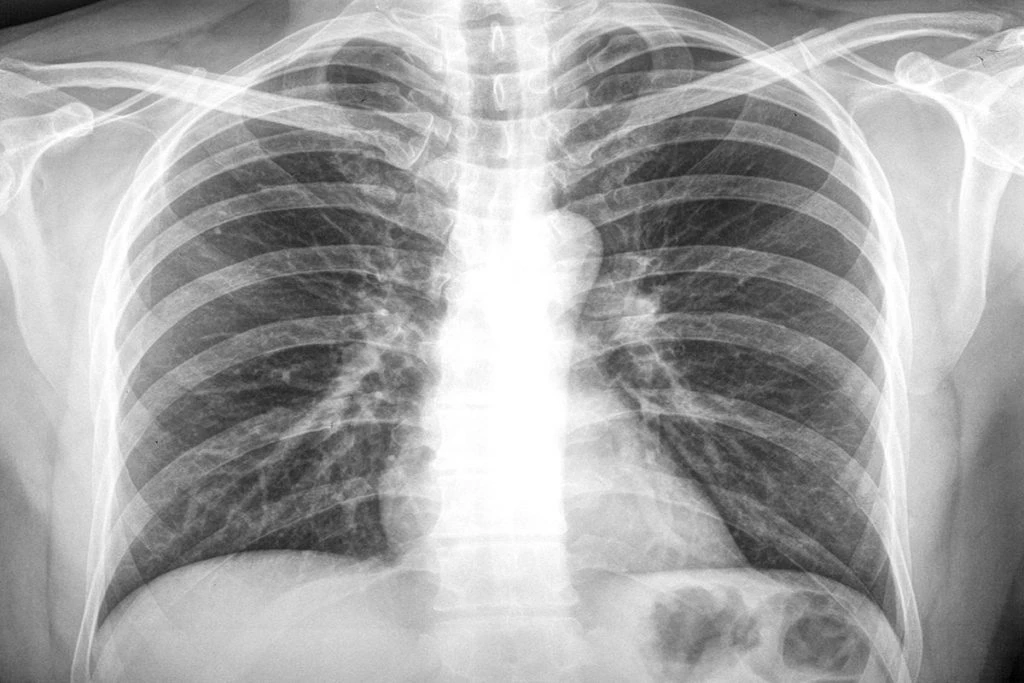

การตรวจคัดกรองมะเร็งปอด ?

การตรวจคัดกรองจะช่วยให้แพทย์สามารถตรวจพบและรักษามะเร็งได้ตั้งแต่เนิ่นๆ แต่ในปัจจุบันยังไม่มีวิธีการตรวจสอบมะเร็งปอดแบบง่ายหรือด้วยตนเองดังเช่นมะเร็งเต้านม อย่างไรก็ตามมีการตรวจสอบใหม่ที่เป็นการตรวจเอกซเรย์คอมพิวเตอร์แบบใช้ปริมาณรังสีต่ำ (low-dose helical computerized tomography) ซึ่งสามารถนำมาใช้ในการตรวจคัดกรองและวินิจฉัยได้

การตรวจเบื้องต้นและการวินิจฉัยมะเร็งปอด ?

หากมีอาการที่เข้าข่ายของโรคมะเร็งปอด แพทย์จะทำการตรวจร่างกาย ตรวจเสมหะ เอกซเรย์ปอด หากพบความผิดปกติ อาจต้องทำการตรวจเพิ่มเติมเพื่อยืนยันการวินิจฉัย

การตรวจวินิจฉัยด้วยรังสี

การตรวจด้วยเครื่องเอกซเรย์คอมพิวเตอร์ (CT scan) และการตรวจโดยใช้คลื่นแม่เหล็กไฟฟ้า (MRI) เป็นวิธีที่ช่วยให้แพทย์หาตำแหน่งและขนาดของก้อนเนื้อที่ผิดปกติในบริเวณปอดได้